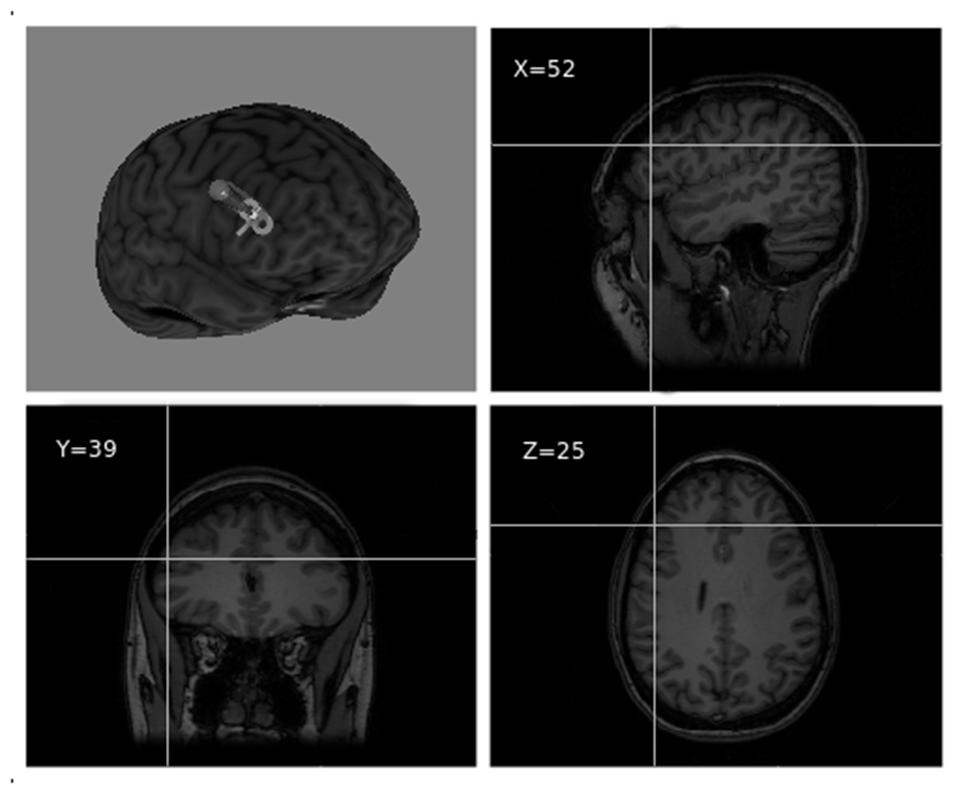

The stimulation target was set to Montreal Neurological Institute (MNI) coordinates x = 52, y = 39, z = 25, corresponding to the point of maximum grey matter increase in the right DLPFC as a result of training in the video game (Kühn et al., 2013; see Figure 2). Coordinates were individually adjusted for each participant based on their structural MRI. For target location and TMS guidance, we used the BrainSight 2 neuronavigation system (Rogue Research, Montreal, Canada).

Figure 2

Right dorsolateral prefrontal cortex (DLPFC) TMS target visualized over a 3D MRI reconstruction of a participant’s head (reproduced with participant’s permission).